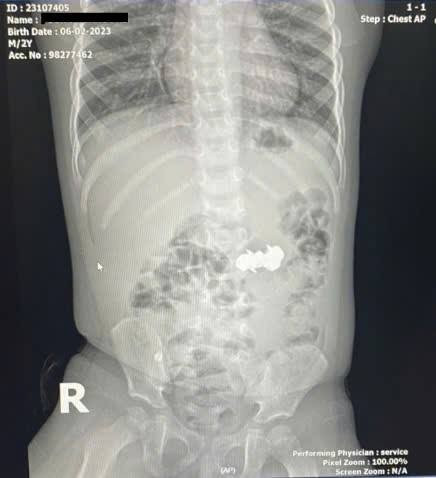

Bé trai nuốt 4 viên đinh nam châm đầu nhọn nguy hiểm. Ảnh BV

Bé D.H.P. (2 tuổi, trú tại Nghệ An) được gia đình đưa đến viện trong tình trạng nghi ngờ nuốt dị vật trong lúc chơi đồ chơi. Kết quả chụp X-quang bụng cho thấy trong ổ bụng có bốn dị vật kim loại nhỏ hình tròn, có đầu nhọn, nghi là đinh nam châm. Các viên nam châm này đã hút dính nhau trong đường tiêu hoá, tạo nên nguy cơ đặc biệt nghiêm trọng.